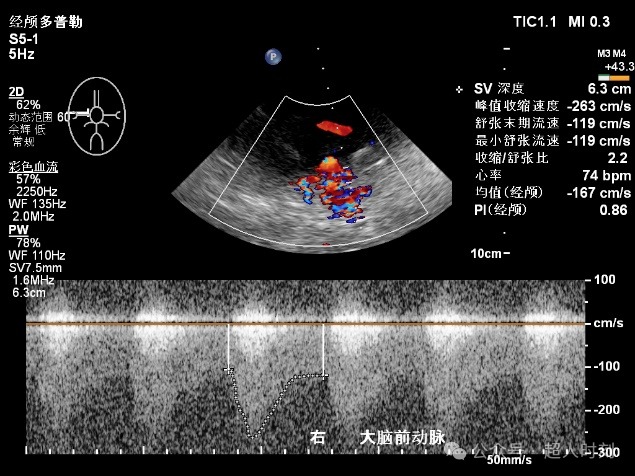

患者,男性,78岁,因“反复头痛头晕‚伴右眼黑朦1+年,肢体麻木偶感上肢无力6+月”入院。颈动脉彩超:右颈内动脉明显狭窄(狭窄率70%-99%),双侧颈总动脉多处狭窄(狭窄率<50%)。TCCD:颅内多支动脉狭窄(见图5)。

图5c 右大脑后动脉狭窄

图5d 右大脑后动脉血流增快频谱(VP:140cm/s)

图5e 左大脑中动脉狭窄频谱(VP:178cm/s)

图5f 右大脑前动脉狭窄频谱(VP:263cm/s)